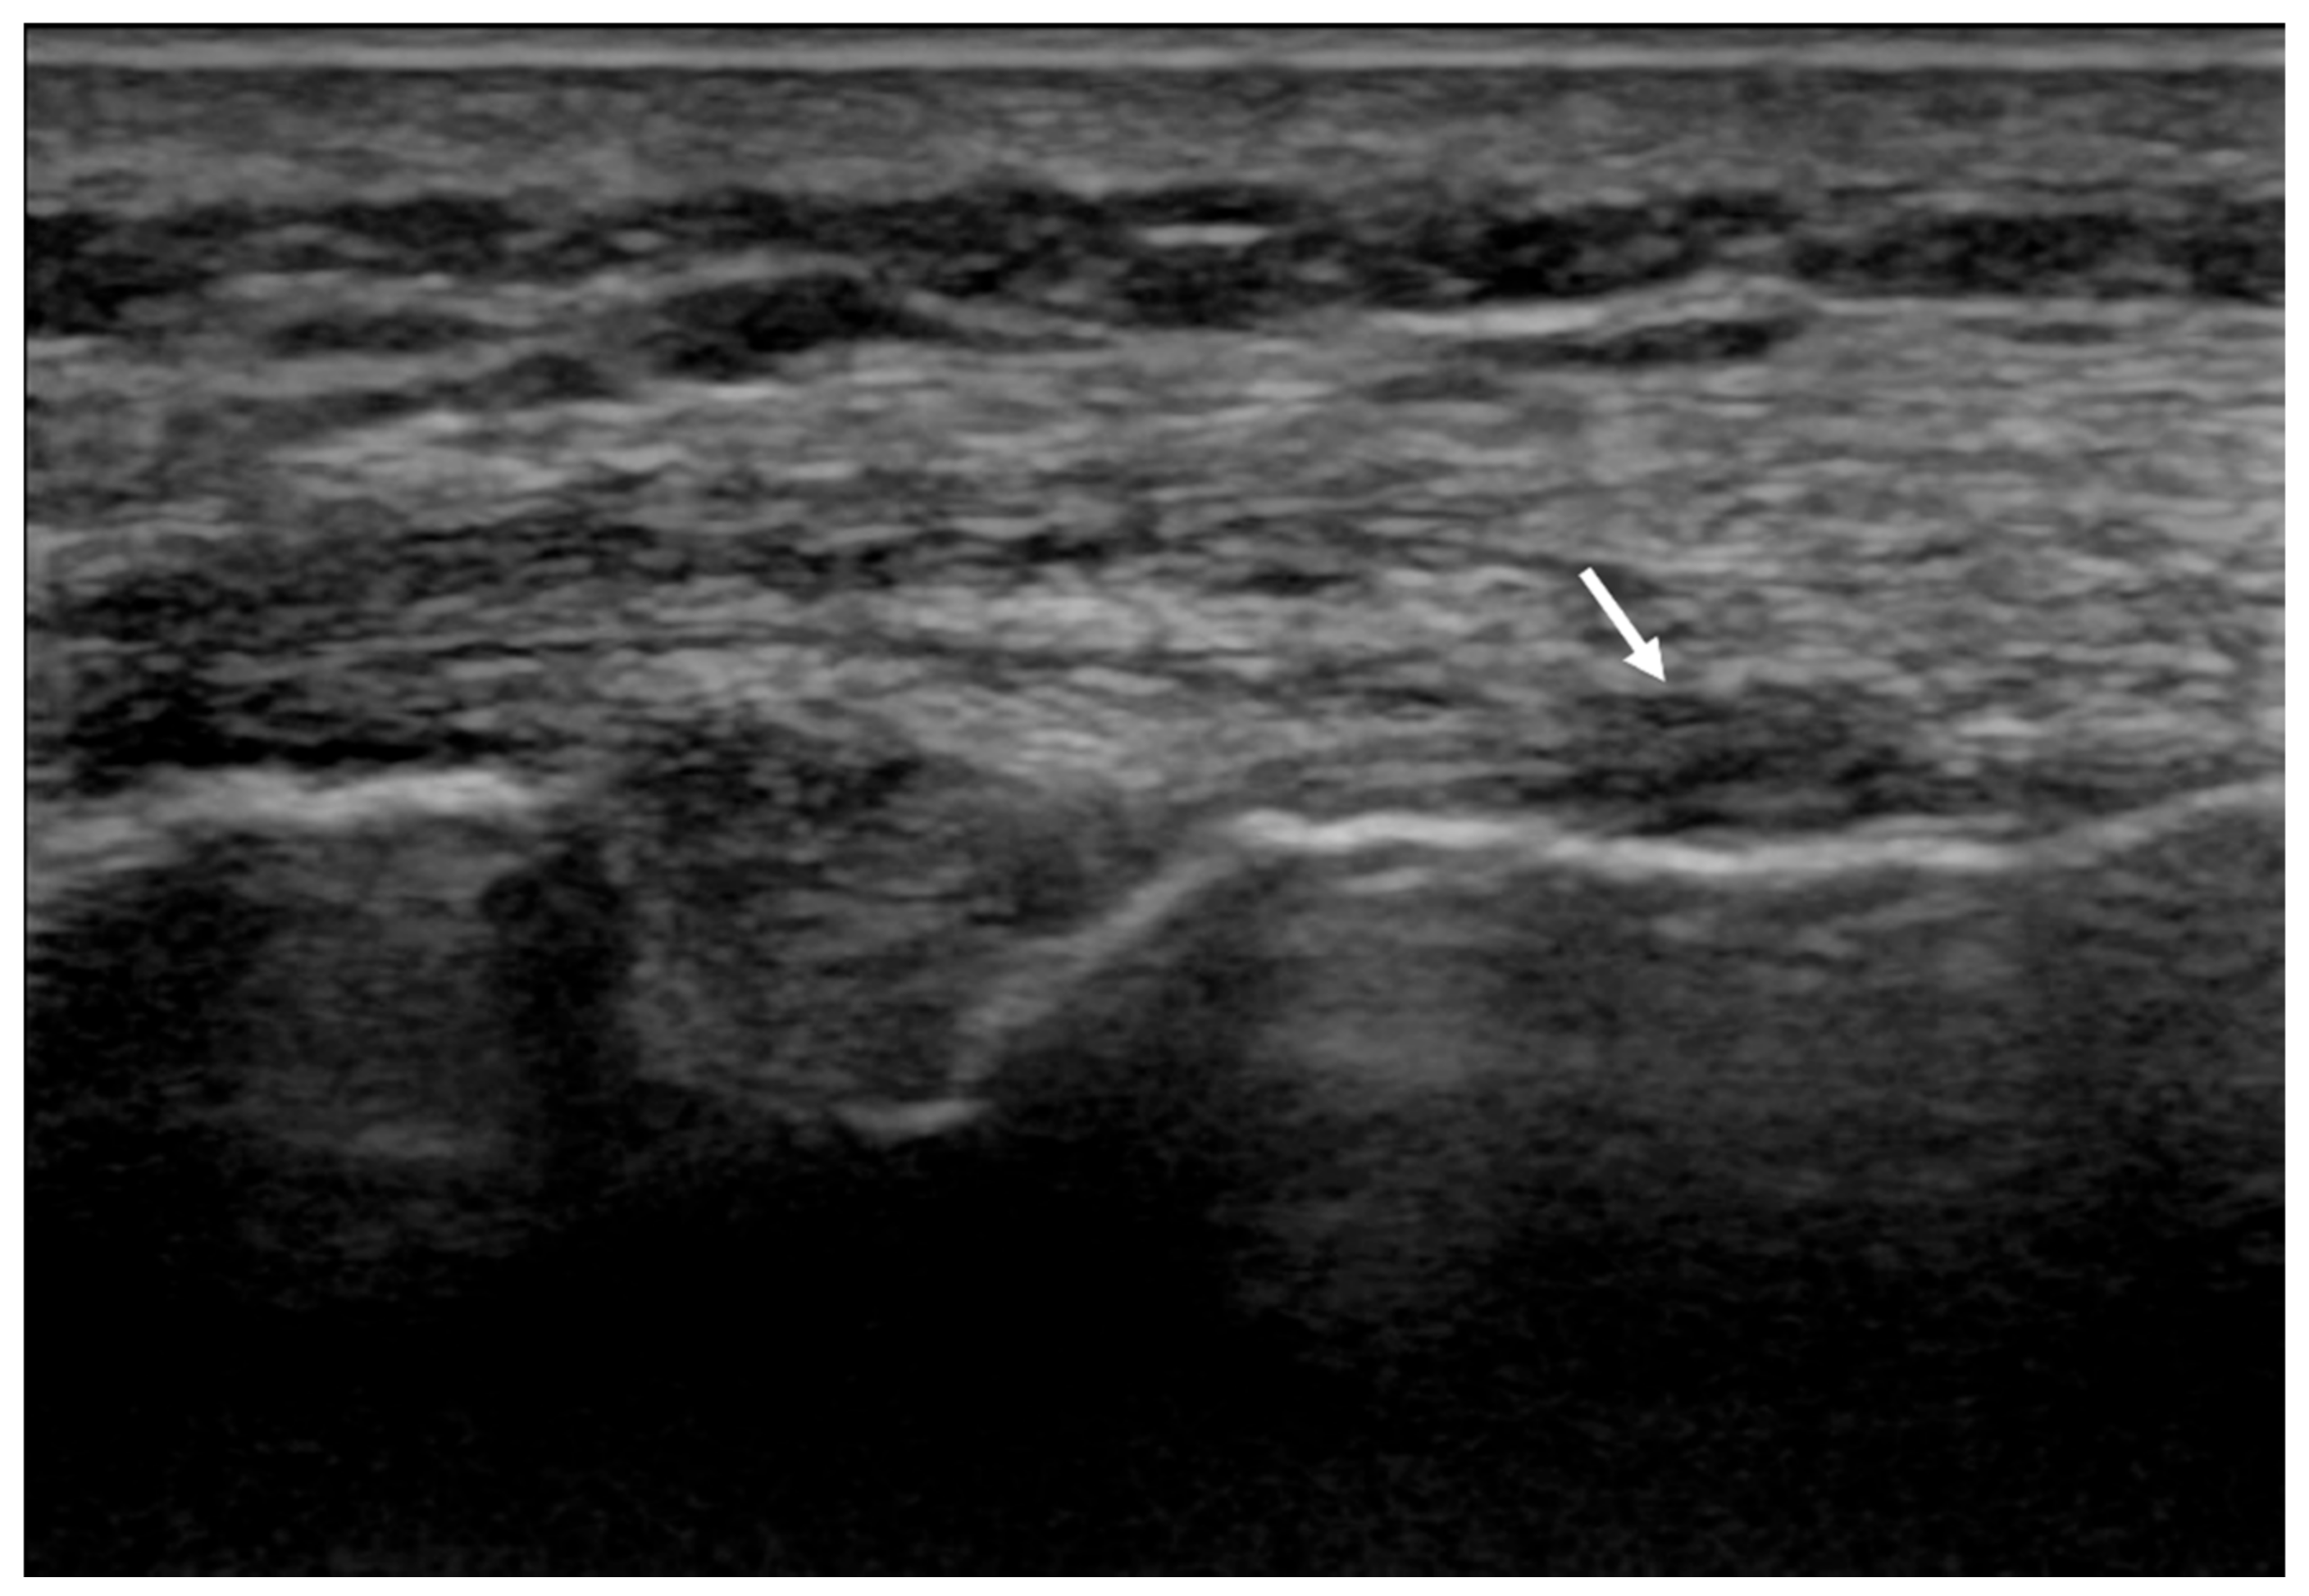

2. Materials and Methods

3. Results